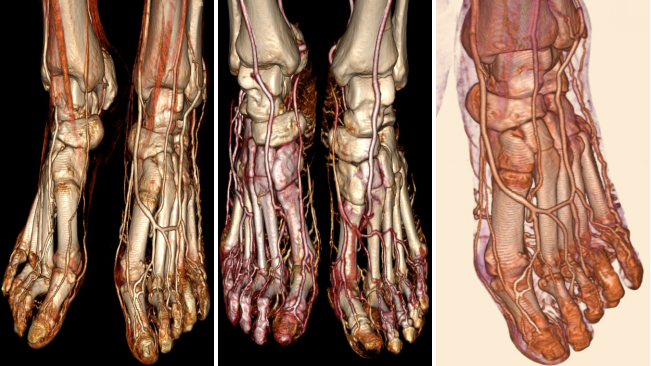

病例一 女,56歲, 足部間斷性麻木一周余。

單圈不動(dòng)床容積掃描完成低劑量全足CTA掃描, 足背血管網(wǎng)及足底動(dòng)脈弓顯示清晰。

掃描下肢血管的時(shí)候, 由于下肢血流速度較為緩慢, 常規(guī)做完下肢CTA以后, 足部血管末梢經(jīng)常沒(méi)有充盈。

640層寬體探測(cè)器CT只需一圈掃描,就可以覆蓋全足;一圈實(shí)現(xiàn)足背動(dòng)脈的高清成像,掃描劑量也很低, 僅僅為0 . 3 m SV。